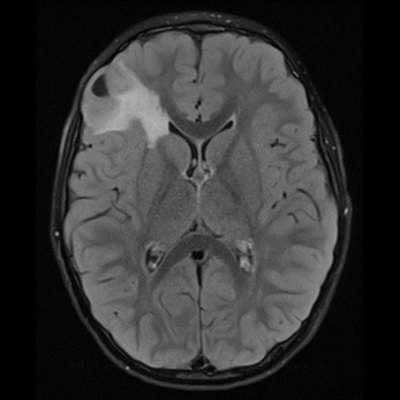

DNET:Özellikle erkek çocuk ve nöbet öyküsüyle gelen hasta kortikal yerleşim ve t1 ağırlıklı serilerde hipointens t2a ve flair serilerde ise hiperintens görülmesi bu tanıma uymaktadır. Hastaların 5’te birinde frontal lobda da tutulum olabilir. Lezyon çevresinde ödem ya da içerisinde kalsifik odak izlenmemiştir:

DNET:Özellikle erkek çocuk ve nöbet öyküsüyle gelen hasta kortikal yerleşim ve t1 ağırlıklı serilerde hipointens t2a ve flair serilerde ise hiperintens görülmesi bu tanıma uymaktadır. Hastaların 5’te birinde frontal lobda da tutulum olabilir. Lezyon çevresinde ödem ya da içerisinde kalsifik odak izlenmemiştir.